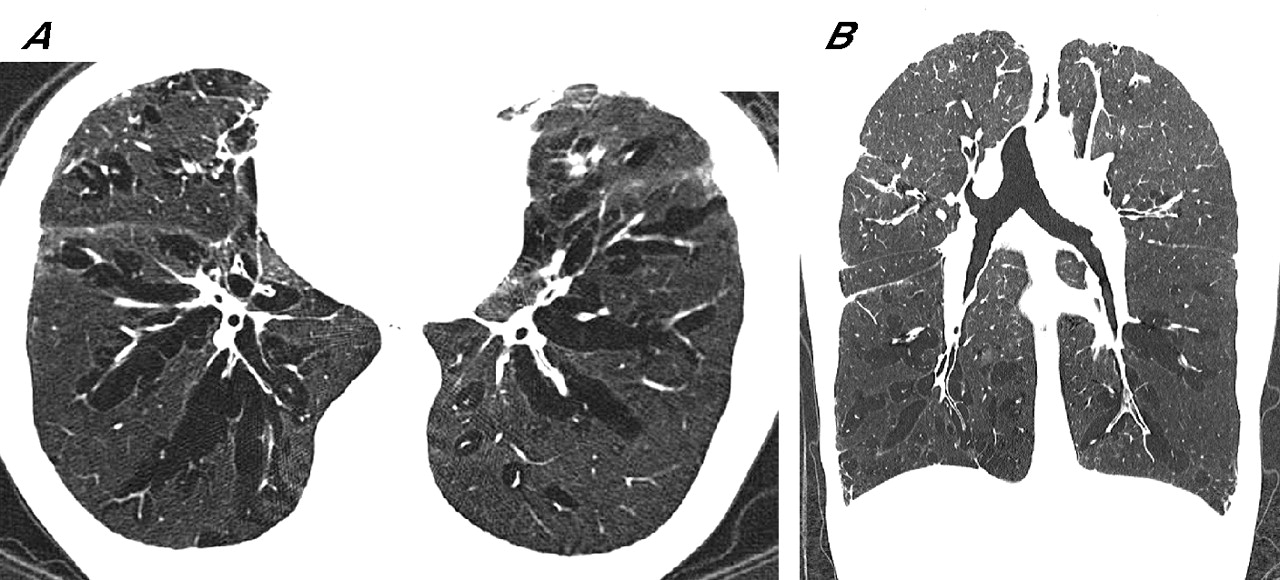

Image Hyperinflation Lungs Definition It happens when you can’t exhale, or push out all of the air. Lung hyperinflation describes when the lungs expand beyond normal due to air being unable to escape the lungs. The trapped air takes up space, so it’s harder. It develops from damage to the air sacs in the lungs,. It happens when too much air gets trapped inside. Hyperinflation Lungs Definition.